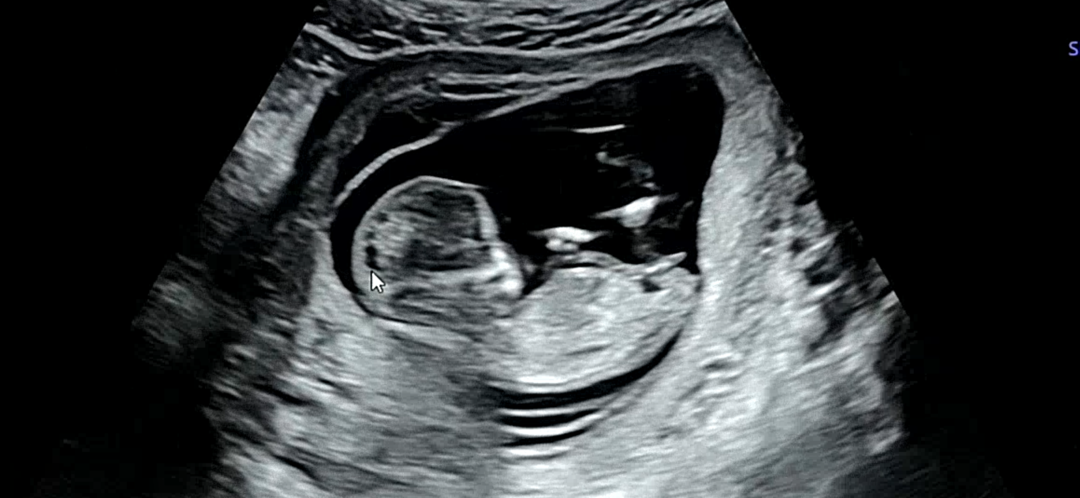

[12주 2일] 각도법고수님들!!!뾰족하게 나온게 제가 생각하는 ㄱㅊ가 맞을까요?!

아님 탯줄일까요…?🥹 성별 상관없지만 너무 궁금하긴 하네요 ㅎㅎㅎ

저는 딸같아요! ㅎㅎ

아들 맞는 것 같아요 ㅎㅎㅎ